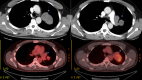

Sarcoma is a malignant tumor arising from the mesenchymal tissues such as striated skeletal and smooth muscles, adipose tissue, bone, cartilage, and synovial tissue. The synovial subset of primary pulmonary sarcoma is very rare and is only described in a handful of cases. Our case describes the diagnostic approach and treatment regimen for a 49-year-old male with no significant past medical history. The diagnosis of a primary pulmonary synovial sarcoma was made through the use of endobronchial ultrasound (EBUS), transbronchial needle aspiration (TBNA), histologic analysis, and immunostaining. The treatment utilized a multimodal approach including resection, chemotherapy, and radiotherapy.